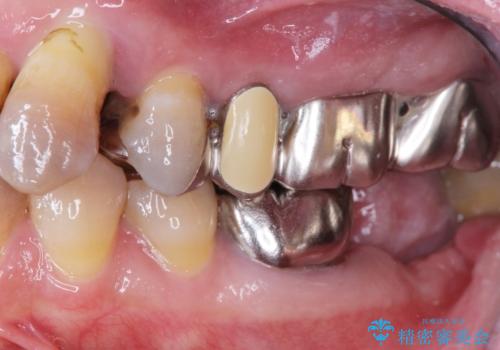

- 他院で上顎は全て抜歯し、入れ歯にする必要があると言われ相談に来院されました。

検査の結果、重度の歯周病であることから保存が難しい歯は抜歯を行いインプラントを、残すことが可能な歯には再生治療を含めた歯周病治療を行いより多くの歯を残す歯周病治療を計画します。

上顎は、残っている前歯も揺れがあり残すためにはクラウンでつなぐ歯周補綴が必要な状態です。

また咬合負担に不安のある前歯を助けるためにも、臼歯部にインプラント補綴を行いしっかりとかめる状態とすることも大切です。